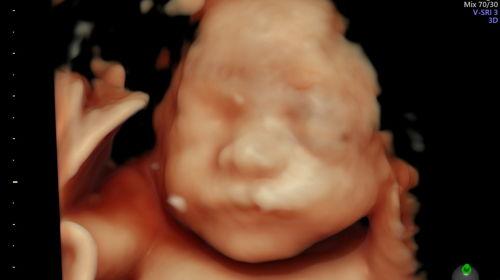

Kelsey's Baby Registry